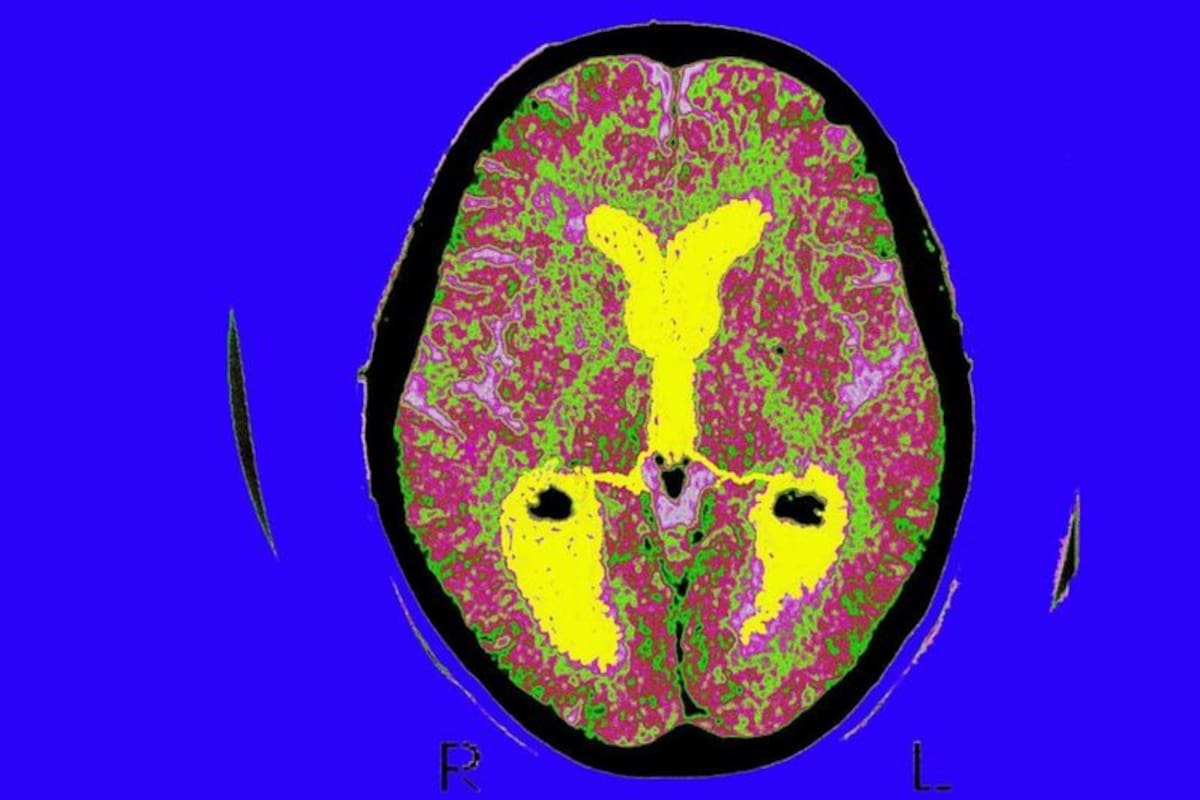

Son solo 60 las personas que hasta el momento han sido identificadas con esta condición, pero el motivo por el cual se genera aún no es del todo claro. Lo que sugieren las investigaciones realizadas es que hay un aumento en el tamaño del lóbulo temporal -el que ayuda a procesar la memoria-, como también en el núcleo caudado -el que ayuda a aprender-.Y aunque algunos deseen recordar cada parte de su vida, Sharrock, quien también tiene autismo, comenta que no todo es tranquilo para ella. El poder revivir las historias de manera tan exacta puede causar no solo dolores de cabeza, como es el caso de Sharrock, sino dificultad para dejar ir experiencias traumáticas o una desconexión repetitiva del mundo actual por encerrarse en los recuerdos.